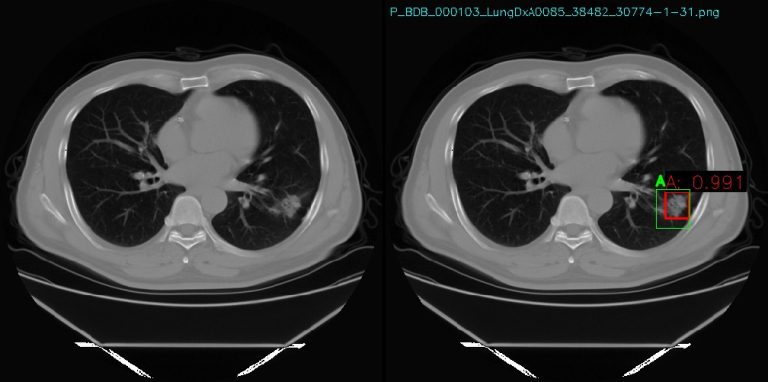

O projeto PRIMED, que está a ser desenvolvido no Laboratório de Processamento de Imagem Médica, a funcionar no IPS desde o passado mês de julho, recorre a inteligência artificial (IA) e a grandes volumes de dados clínicos e médicos (casos de pacientes), para apoiar os profissionais de saúde na tomada de decisões mais informadas, rápidas e seguras.

Com uma abordagem inovadora, baseada na combinação de técnicas de visão por computador e IA, o projeto PRIMED permite assegurar a conformidade com o Regulamento Geral sobre a Proteção de Dados (RGPD) e com os princípios éticos fundamentais.